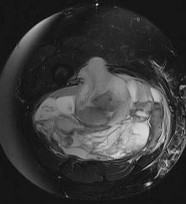

A 15-year-old male presents with deep knee pain awakening him at night. Radiographs show a permeative destructive lesion in the distal femoral metaphysis with a 'sunburst' periosteal reaction and Codman's triangle.

Biopsy confirms high-grade conventional osteosarcoma. What is the most critical prognostic factor for long-term overall survival in this patient?

Explanation

For localized high-grade osteosarcoma, the most important prognostic indicator is the histologic response to neoadjuvant chemotherapy. This is evaluated during the definitive resection. A 'good response' is typically defined as greater than 90% or 99% tumor necrosis. Patients who achieve this level of necrosis have a significantly improved disease-free and overall survival rate compared to 'poor responders' who have extensive viable tumor cells remaining.